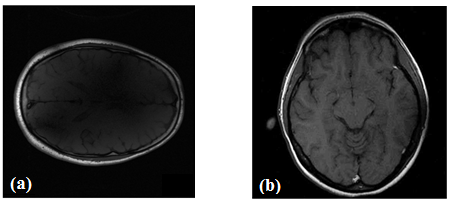

For comparison, both the algorithms (i.e., the DLMRI and our proposed one) were subjected to two different datasets, i.e., the test MR image used in [11] and another MR image, which we name as MRI-1 and MRI-2, respectively. These data are depicted in Fig. 2. Various sampling masks i.e., Random, Cartesian and pseudo radial available in [11] were applied on the reference data in k-space domain to reach different levels of undersamplings. It is noticeable that in pseudo radial mask, a Cartesian grid is used to map the samples on the radial lines to their nearest points on the grid.